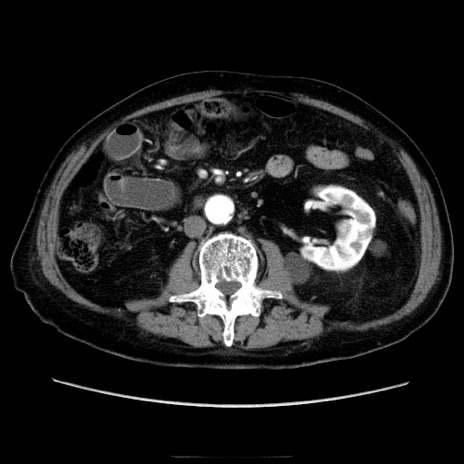

症例21(横断像)

【症例】70歳代男性

【主訴】腹痛

【現病歴】肝硬変・肝細胞癌にてかかりつけの方。約9時間前に食後より腹痛出現。症状が徐々に増悪し、嘔吐出現したため来院。

【既往歴】肝硬変、肝細胞癌(RFA、TACE後)

【身体所見】意識清明、表情苦悶様、BT 36℃、BP 129/78mmHg、P 88bpm、SpO2 97%(RA)、右上腹部から心窩部にかけて圧痛あり、反跳痛なし、筋性防御あり。

【データ】WBC 5800、CRP 0.16